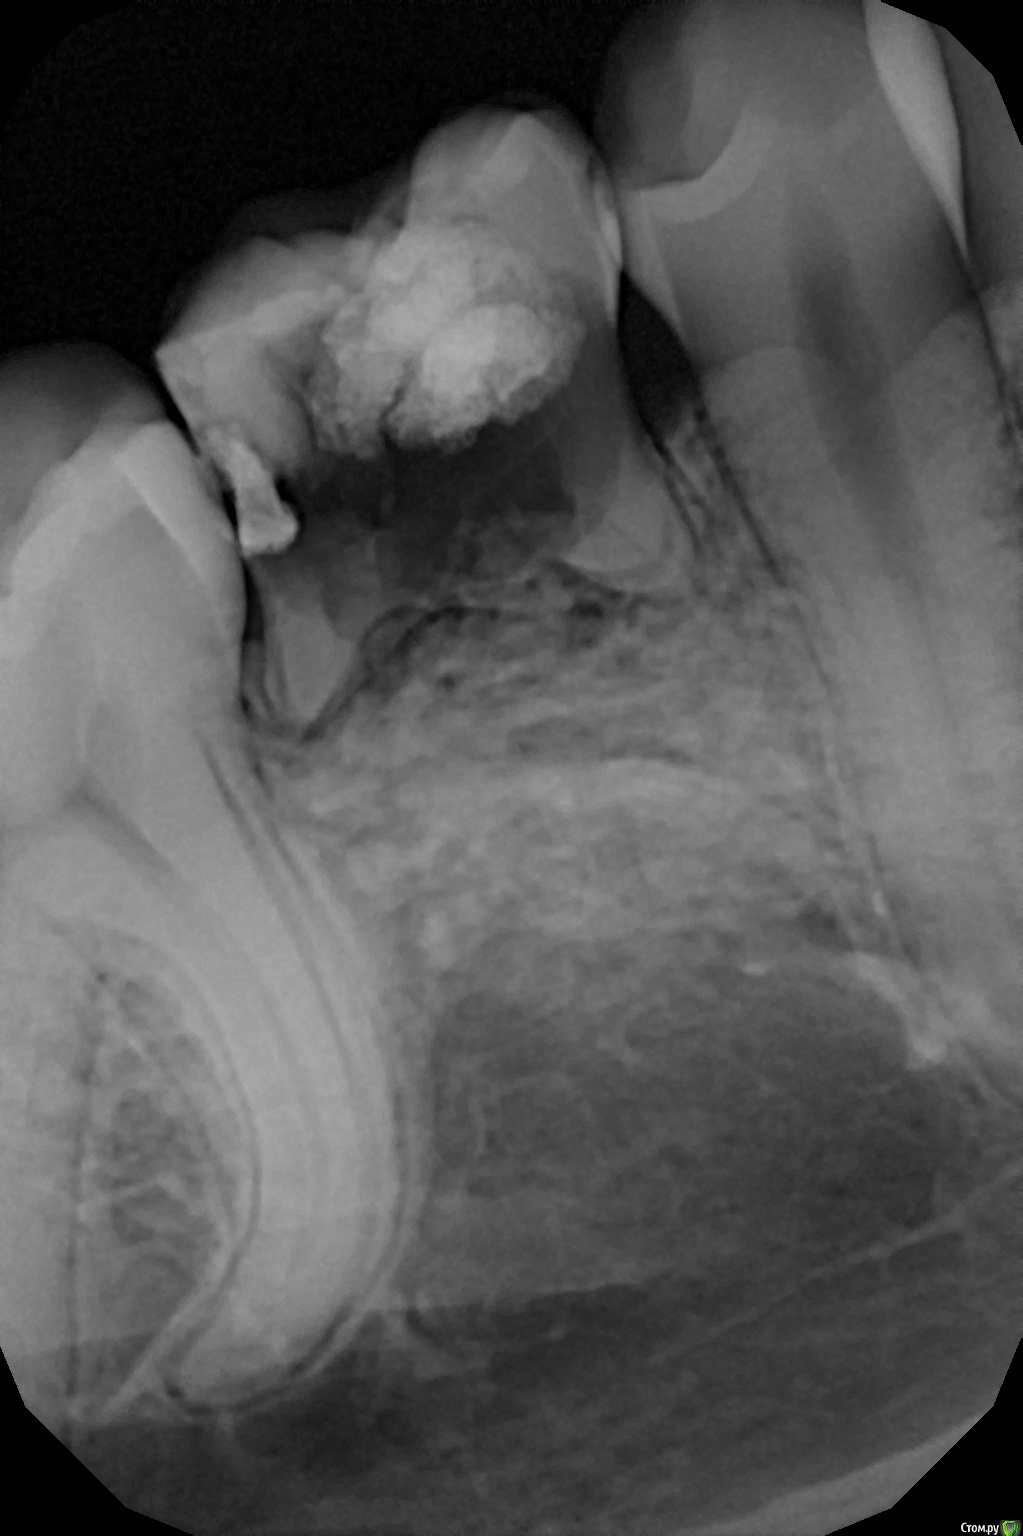

Дарья Буева Опубликовано 21 сентября, 2018 Поделиться Опубликовано 21 сентября, 2018 (изменено) Здравствуйте! Мне 21 год. Первый раз лечила зубы у стоматолога в 18 лет, ставили пломбу на сегодняшний проблемный зуб. Спустя год -два появилась щель между десной и зубом. Особого дискомфорта не было. Никак не мешалось. И на днях откололся кусочек зуба у десны, была кровь. На следующий день, врач спилил стенку зуба с отколом, копался в зубу , сказал что весь сгнил, а десна заросла.Начал прижигать десну, чтобы ЧТО -ТО УВИДЕТЬ. не смог, крови много,не видит, отправил на ренген ( что я считаю нужно было делать изначально), поставил временную пломбу . К нему я больше не возвращалась. Пошла в клинику.Снимок показал, что это молочный зуб и зачатка ниже нет. Далее предложение удалять зуб и ставить имплант, либо мост. Другой врач с Челябинска сказал только имплант (удаление зуба и ждать пол года заживления)Подскажите пожалуйста , какой лучше вариант для моего несчастного зуба. И возможны ли последствия для других зубов.Большое спасибо заранее. Изменено 21 сентября, 2018 пользователем Дарья Буева Ссылка на комментарий